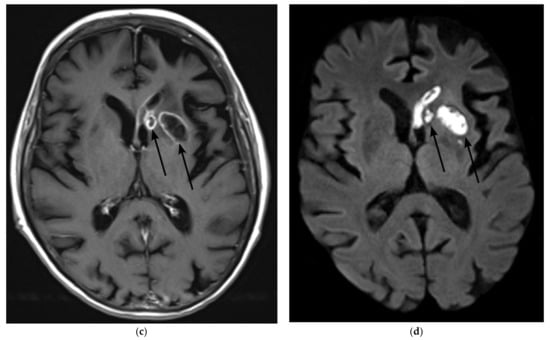

2. Case Presentation